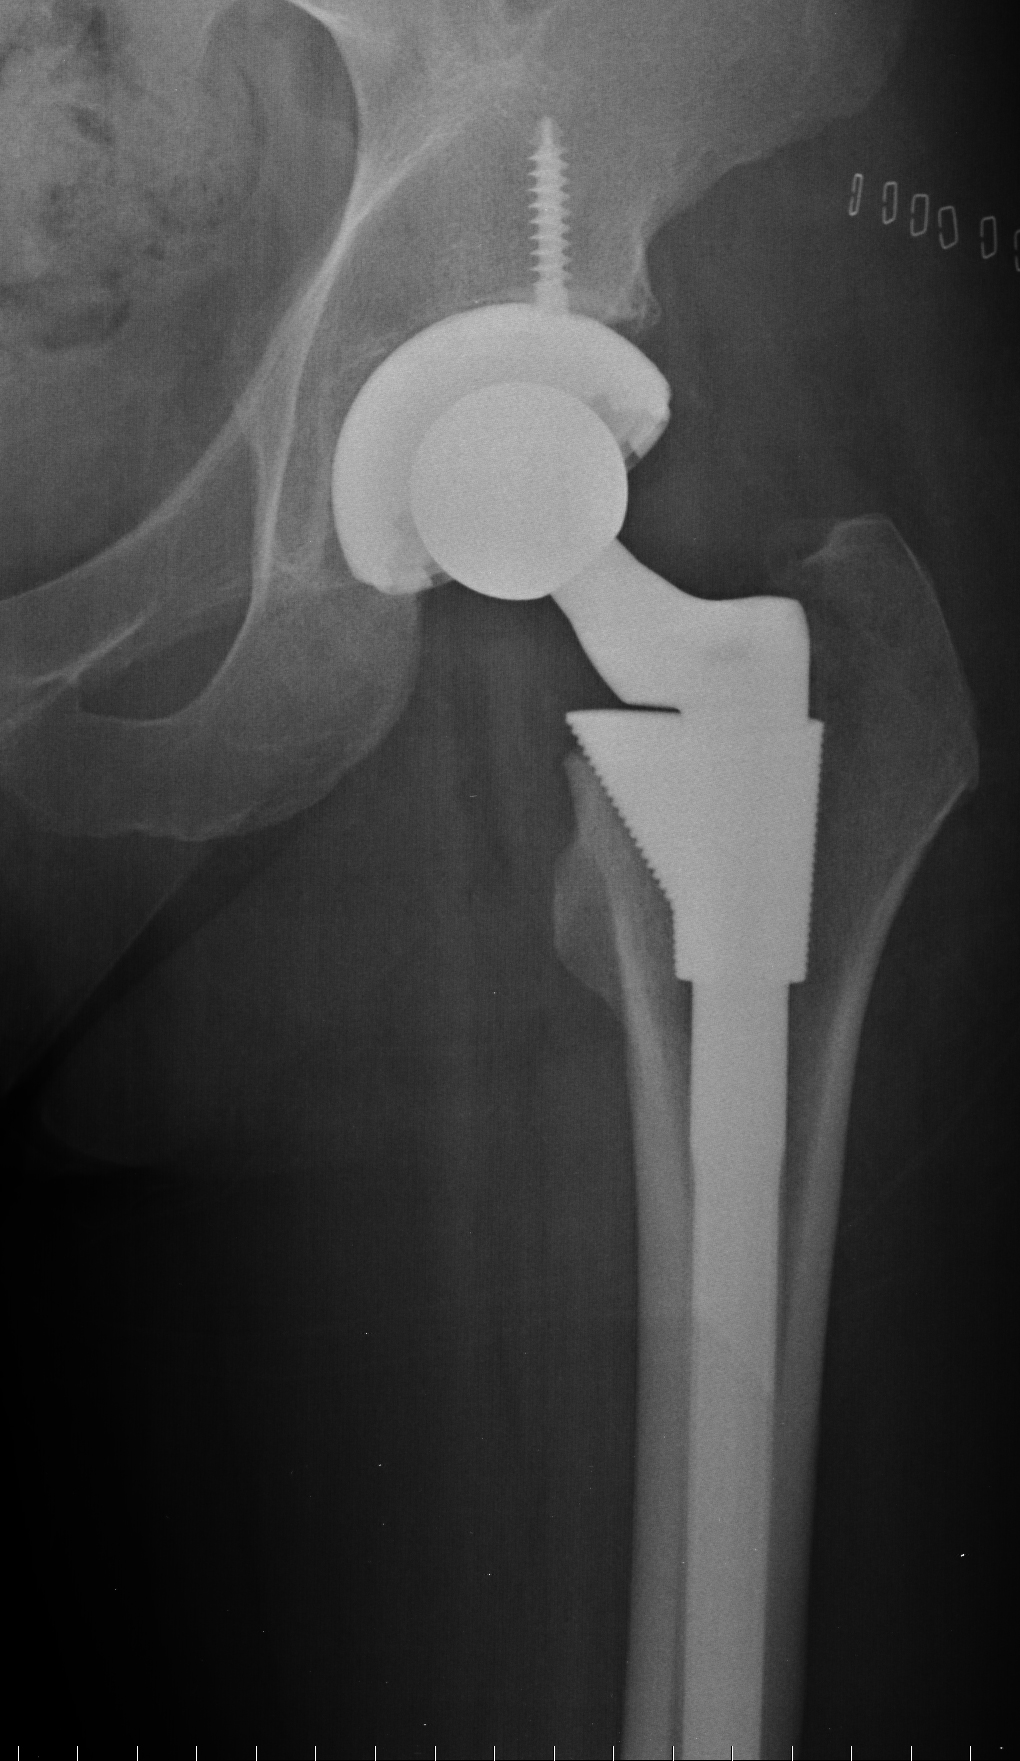

If you are suffering from severe pain in your hip joints, this may be a result of one or more possible conditions: osteoarthritis or degenerative joint disease, rheumatoid arthritis, osteonecrosis, tumors, fractures, or various other injuries. Many of these problems develop as an inevitable part of the aging process, while others result from accidents, sports injuries, dietary deficiencies, and numerous other disorders. All of these issues can be debilitating for a person at any age or stage of life, and no matter what precautions might be taken to avoid joint deterioration or damage, sometimes surgery is an inevitable solution.

You may be wondering, “How do I know if I need total hip replacement?” Among the primary indicators that a surgical procedure may be necessary, constant pain that limits your ability to move around freely should be considered a good reason to talk to your doctor about the possibility of hip surgery. Thousands of patients around the United States receive hip replacement surgery every year, and the success rate for this type of procedure is increasingly high, especially among patients with no additional serious health complications. While you may be determined by your physician to be in good enough shape to undergo surgery and recover quickly, it may be the case that you only need a more minor surgery, rather than a total hip replacement. A thorough evaluation by the hip specialists at Rothman Orthopaedic Institute will help you figure out the most appropriate treatment plan for you.

Not every fracture, deterioration, or case of arthritis is due cause for a doctor to recommend hip replacement surgery for a patient. In many cases, a minimally invasive procedure will succeed in reducing or eliminating the pain and difficulties experienced by someone with a relatively minor condition. Some patients tend to benefit from canes, walkers, and wheelchairs, at least for a long enough period of time to delay surgery until it becomes absolutely necessary. For patients with constant pain and difficulty with everyday movement, however, total hip replacement surgery is inevitable.